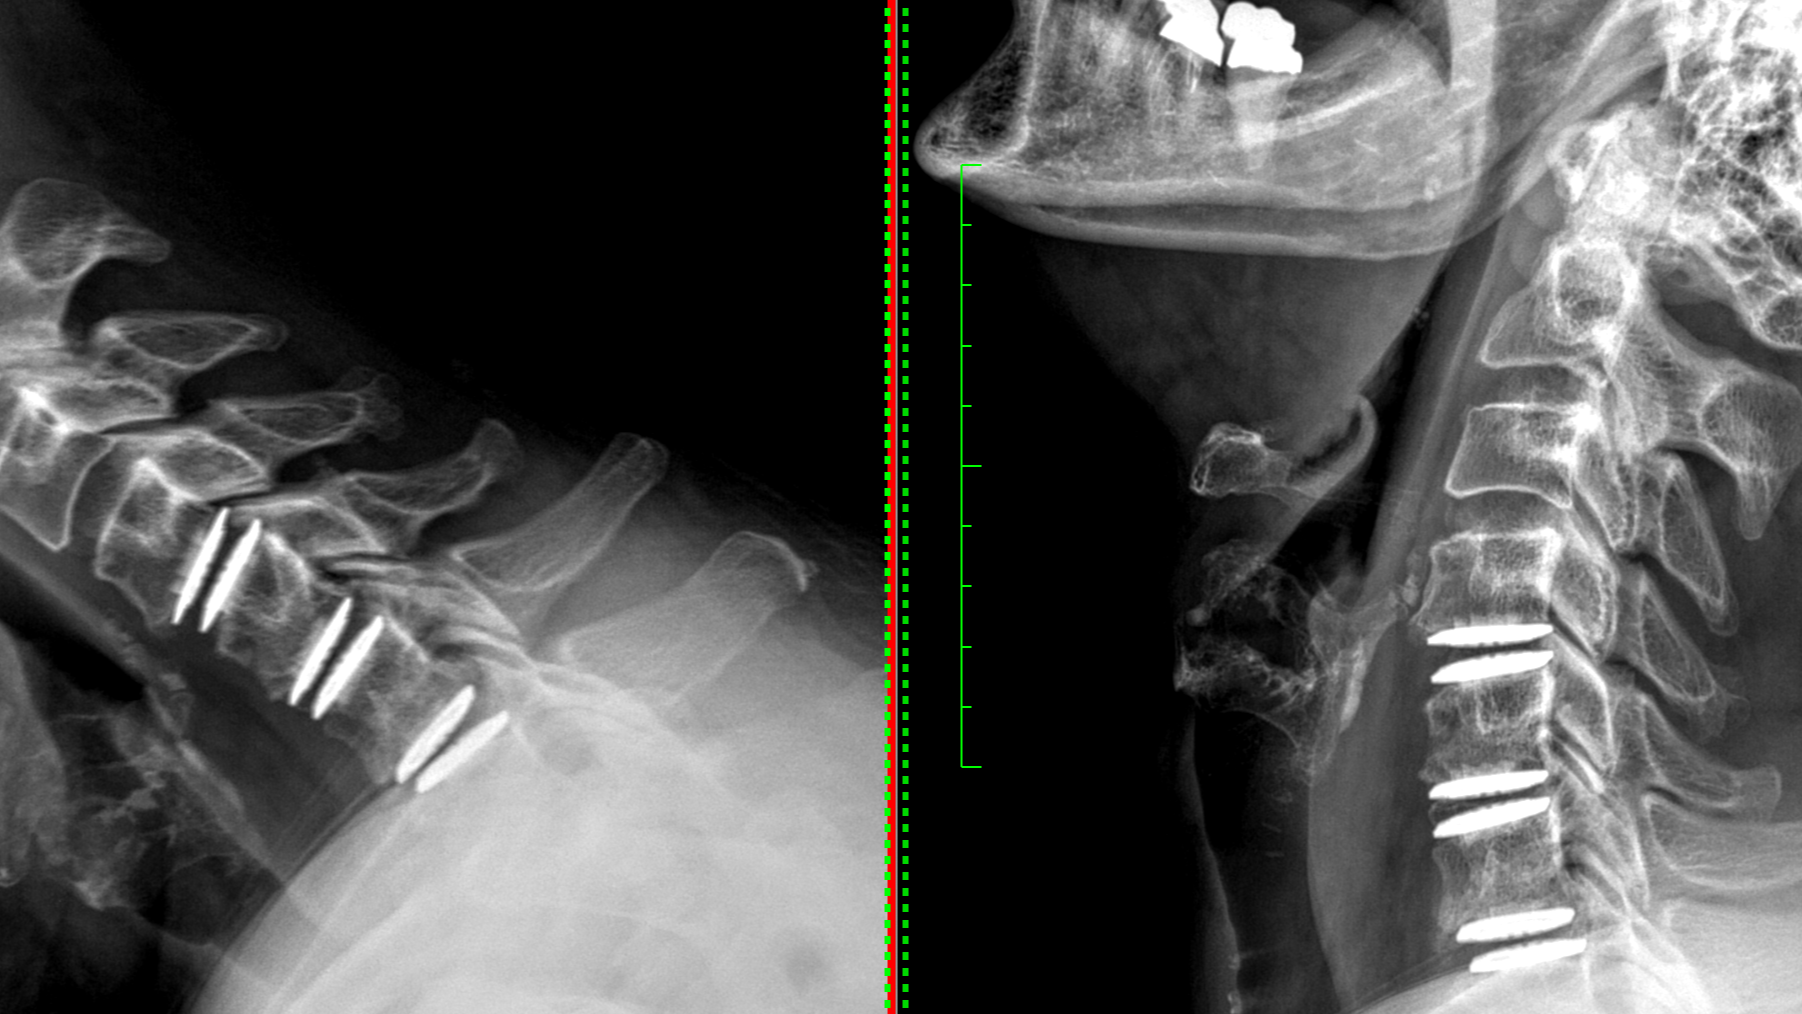

Our ongoing commitment to functional research focuses on evaluating the safety and efficacy of emerging technologies in spinal surgery through both prospective and retrospective clinical studies. We aim to identify the devices and techniques that most effectively improve patient outcomes, using validated clinical metrics and radiographic imaging.

BAGUERA® C Cervical Disc Replacement Clinical Trial

A multi-center study evaluating the safety and effectiveness of the BAGUERA® C artificial cervical disc.Synergy Disc vs. ACDF in Two-Level Symptomatic Cervical DDD

A historically controlled pivotal trial comparing the Synergy Disc to anterior cervical discectomy and fusion.M6-C™ Artificial Cervical Disc Two-Level IDE Pivotal Study

Hybrid Constructs in Cervical Spine Surgery

Retrospective analysis evaluating outcomes of hybrid constructs that combine fusion and motion-preserving technologies in the cervical spine.Premia Spine TOPS™ System in the Ambulatory Surgery Center (ASC) Setting

Two-Year Retrospective Bayesian Assessment of Cervical Artificial Disc Replacement Failure Factors. Amir Vokshoor, M.D., Vance Matthews, B.A., Sophia Mostowy, B.A., & Johny Tran, B.A., Western Neurosurgical Society, Scottsdale, AZ, November 2019.